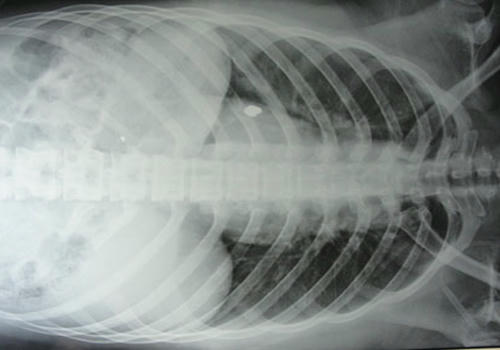

Sau khi cấp cứu, thiếu nữ T. đã qua cơn nguy kịch. Tuy nhiên, T. vẫn phải điều trị vì còn một viên đạn nằm sâu trong phổi, chưa thể phẫu thuật. Các y bác sĩ cần phải chuẩn đoán xem viên đạn nằm chính xác ở vị trí nào và có nguy hiểm tới tính mạng của cô gái hay không. Không còn nguy hại tới tính mạng nhưng tinh thần của cô hiện vô cùng hoảng loạn.

| Viên đạn vẫn nằm trong người nạn nhân |